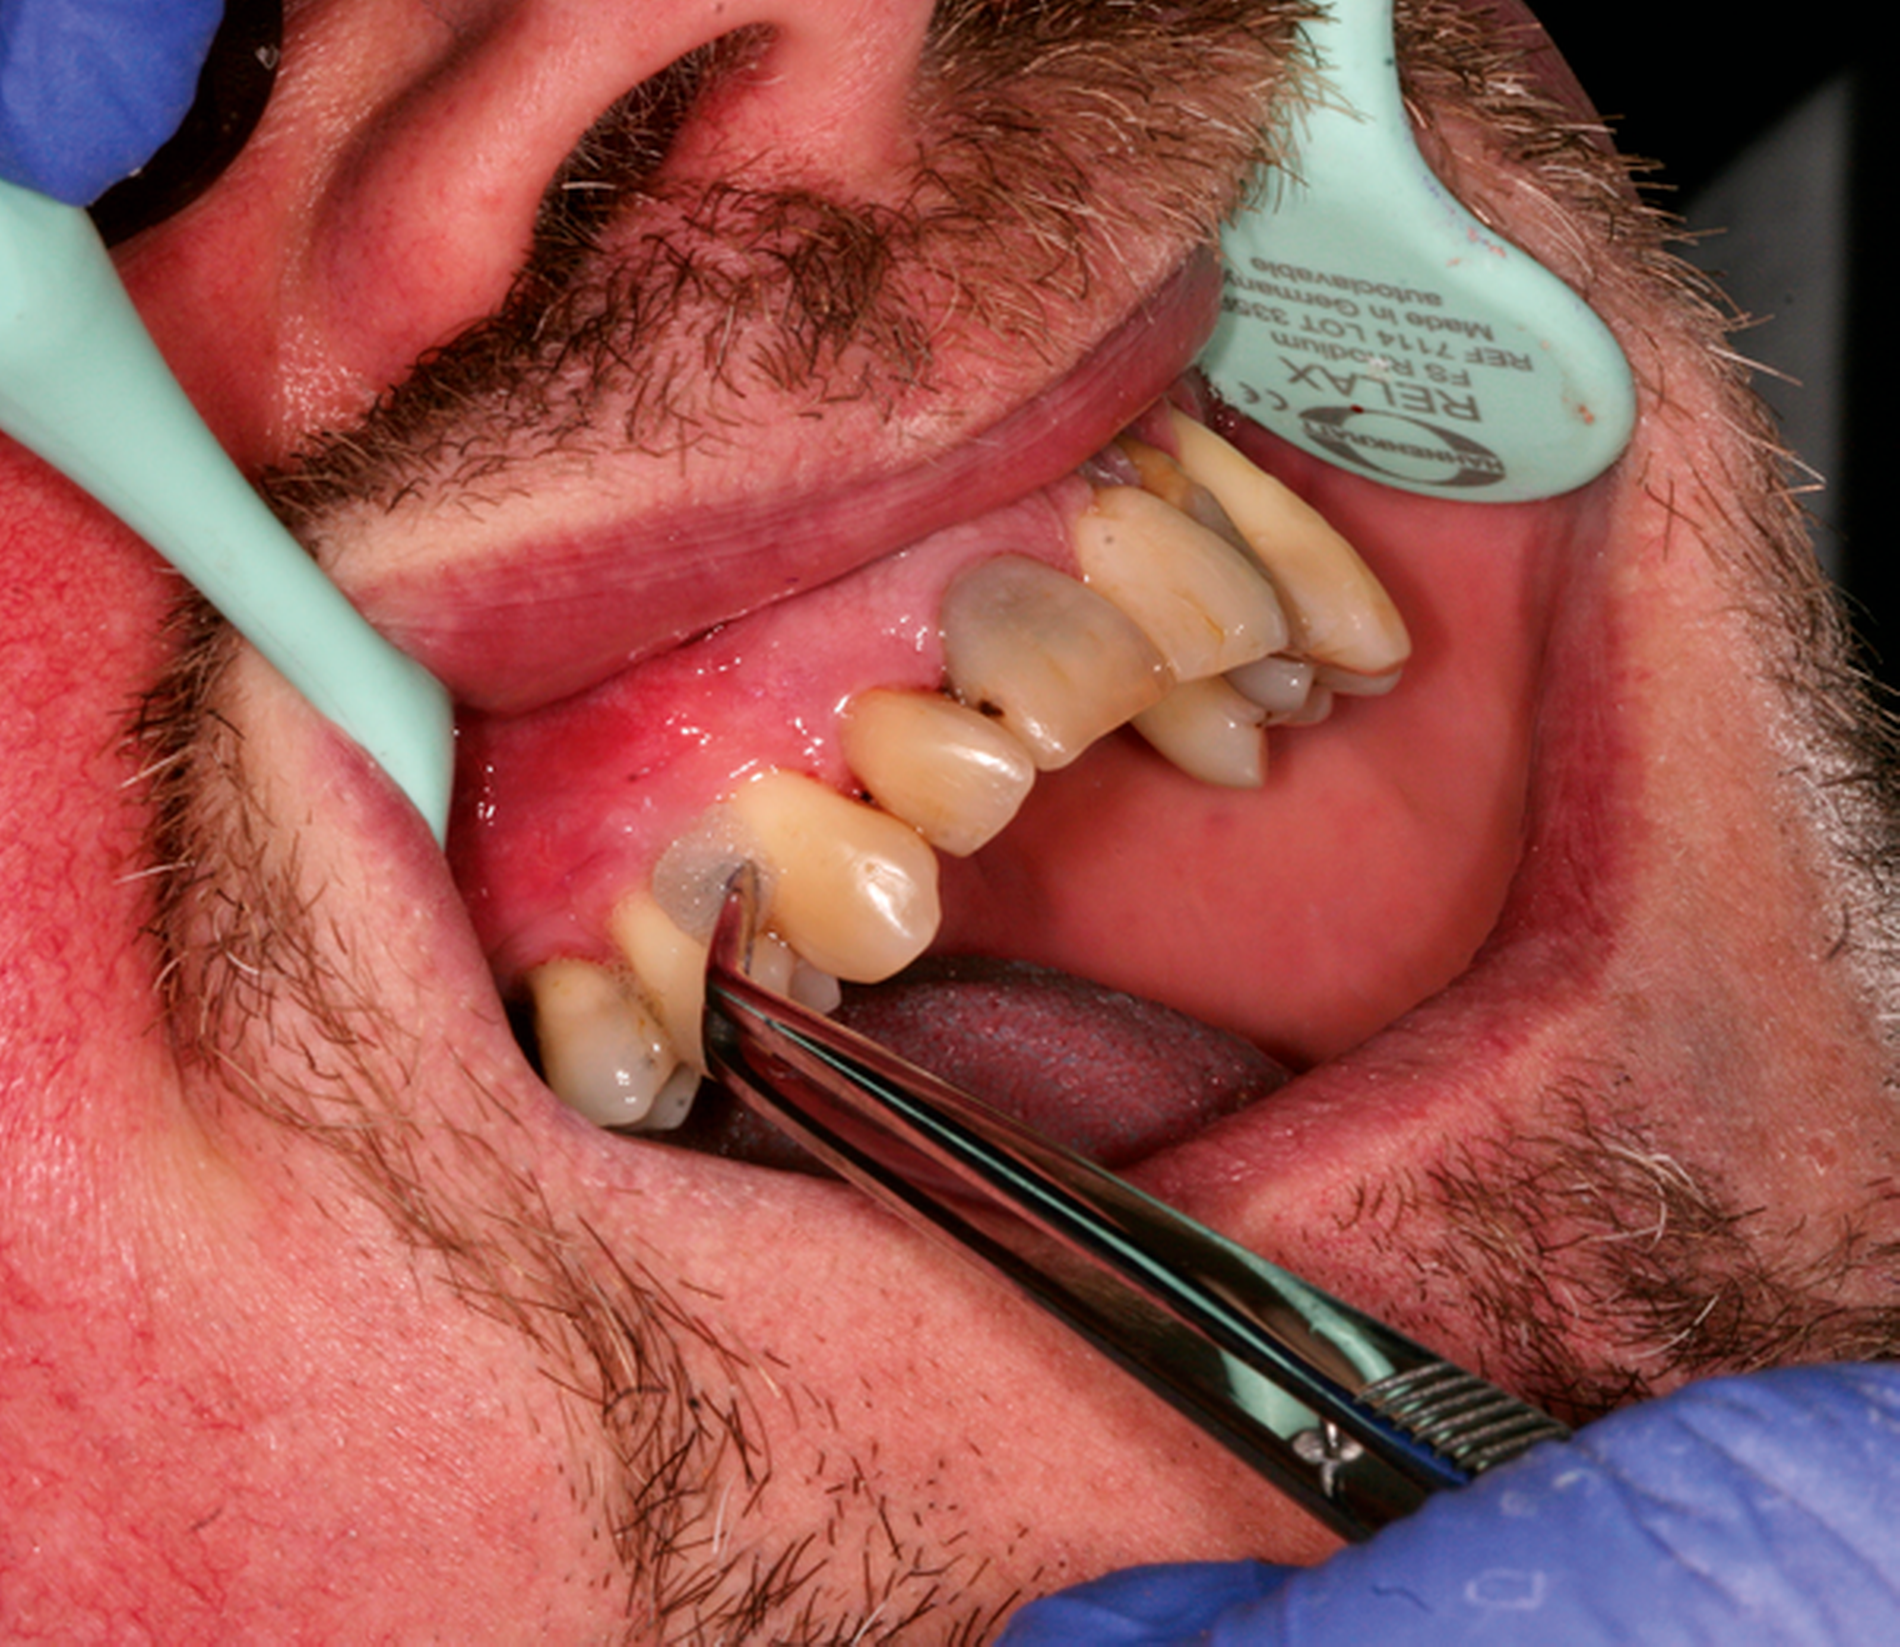

Abb. 1: Interventionen zur Instruktion und Motivation des häuslichen supragingivalen Biofilmmanagments im Rahmen einer UPT-Sitzung: Der 50-jährige Patient befindet sich im dritten Jahr nach der zweiten Therapiestufe und hat ein reduziertes, aber gesundes Parodont.

Häufig können – beispielsweise bei Patienten mit Parodontitis Stadium III oder IV – nicht alle Therapieziele vollständig bei allen Zähnen realisiert werden. Deshalb müssen unter Berücksichtigung der wissenschaftlichen Evidenz individuelle Interventionen in der UPT ergriffen werden, die abhängig vom gingivalen und parodontalen Status sind und dabei die präventiven und therapeutischen Interventionen aus der ersten und der zweiten Therapiestufe kombinieren. Diese professionellen Maßnahmen müssen durch eine Aufrechterhaltung der Motivation zur kontinuierlichen Mitarbeit der Patienten flankiert werden. Das bedingt eine regelmäßige, individuell an die Bedürfnisse des Patienten angepasste Betreuung.